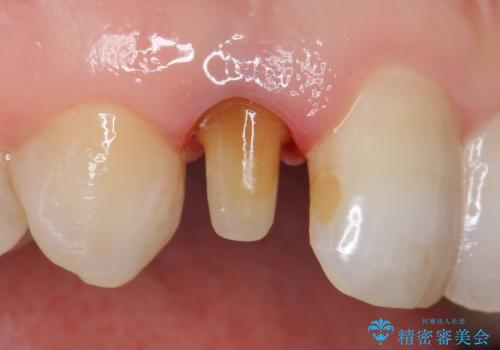

- 右上2番目の歯の変色が気になるといらっしゃった方の症例です。

再根管治療終了後、オールセラミッククラウンによる補綴を行いました。

- オールセラミッククラウン…¥100,000、仮歯…¥10,000、ファイバーコア…¥20,000費用は治療当時の料金となります